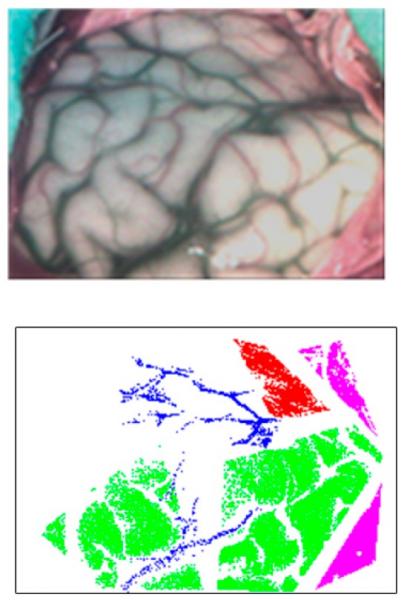

Imagen sintética del tejido cerebral (arriba) y clasificación de los tejidos (abajo); en verde tejido sano, en azul tejido vascular, en rojo tejido canceroso y en rosa dura madre. Fuente: UPM

De esta forma, los investigadores y cirujanos involucrados en NEMESIS-3D-CM están utilizando modelos basados en técnicas de aprendizaje máquina (o más conocido como machine learning) generados a partir de imágenes hiperespectrales para discernir, en tiempo real y durante las mismas intervenciones quirúrgicas, qué tejido está afectado por el tumor y cual permanece sano. Esta tecnología presenta además la ventaja de no ser invasiva, ni ionizante para el paciente.